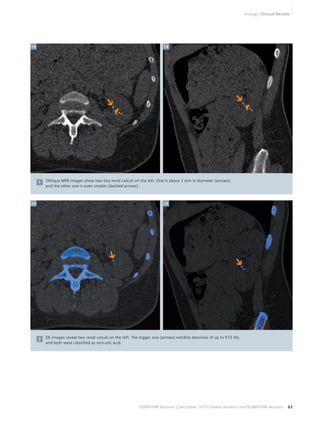

Diagnosis

A few kidney stones in each kidney

were detected. Two of the stones

were clinically significant. Both were

calcium-based stones measuring

5 mm in diameter. One of these

stones was in the lower pole of the

left kidney and the other in the upper

pole of the right kidney, located

within the curve of the ureteric stent

(Fig. 1). On conventional CT images,

the renal calculus is isodense with the

ureteric stent and nearly impossible

to differentiate if they are touching.

The Dual Energy scan allowed to this

stone to be resolved from the adja-cent

ureteric stent (Figs. 2–4).

Comments

The proposed method shows great

promise for distinguishing non-uric

acid stones from ureteric stents. The

method is expected to be valid for at

least 90% of nephrolithiasis cases

based on the current type of urinary

stents.[1] Current Double J stents

are generally made of polyurethane.

Thus, like uric acid (C5H4N4O3), they